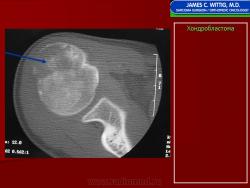

Рентгенологически хондробластома представляет собой сравнительно большой (2-4 см) очаг округлой формы, четко отграниченный от окружающей кости склеротической каймой. На фоне очага в большинстве случаев, но не обязательно определяются плотные включения, напоминающие хлопья ваты.

Рентгенологическая картина. Хондробластома выглядит как небольшой, от 3 до 6 см литический очаг, центрально или эксцентрично расположенный, с четкими контурами, занимающий около половины площади эпифизарной зоны. Хондробластома плоских костей и мелких трубчатых костей больших размеров, может сопровождаться припухлостью мягких тканей, вздутием кости и периостальной реакцией. Распространение процесса на метафизарную зону встречается часто.